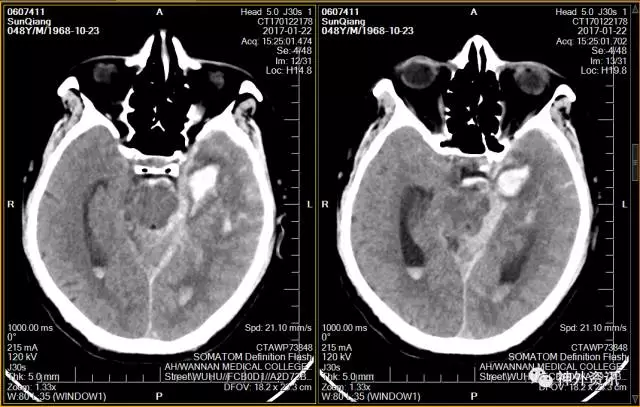

患者:男性, 48岁,主诉:突发头晕伴呕吐7小时余。

查体:神志清楚,GCS评分E4V5M6,Hunt-Hess分级1级,简单言语,对答切题,双侧瞳孔等大等圆,直径约2mm,光反射灵敏,颈亢,四肢活动可,肌力、肌张力正常,双侧巴宾斯基征阴性。

头颅CT示:蛛网膜下腔出血,脑干旁30mm*16mm占位,怀疑颅内动脉瘤可能。

脑动脉CTA示:左侧颞叶血肿,烟雾病伴血流相关性动脉瘤。

(头颅CT示:蛛网膜下腔出血,左侧颞叶血肿)

(增强CT:环池周围凌乱血管影伴瘤样扩张)

(术后头颅CT)